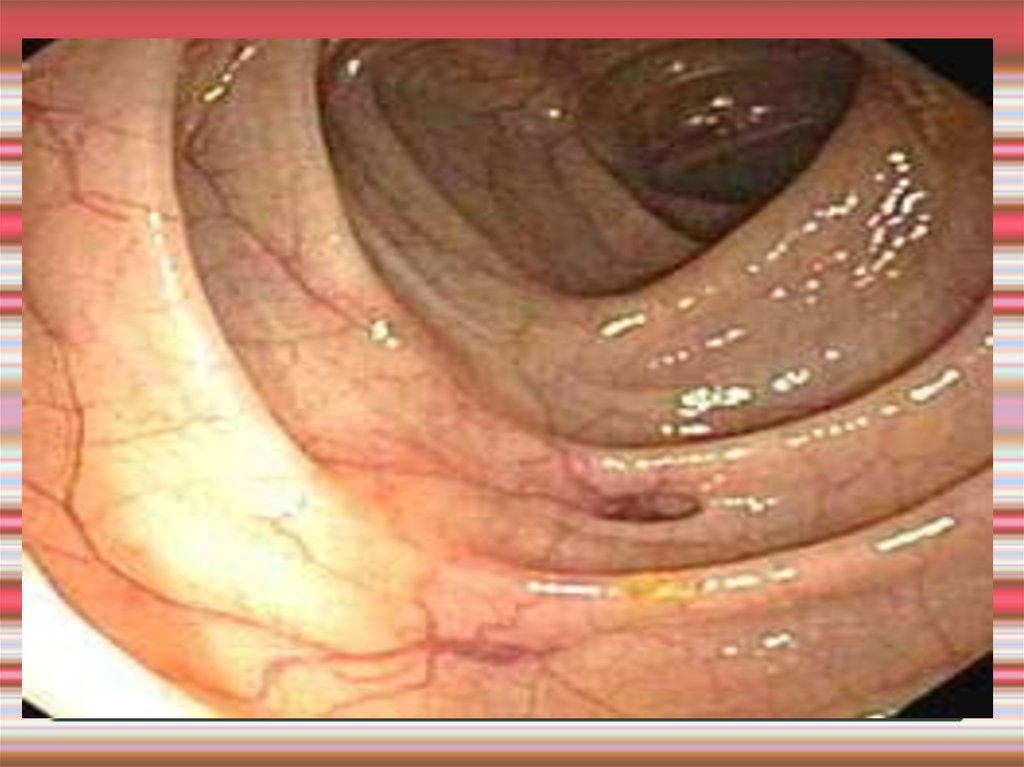

Фиброколоноскопия

7. Диагностика дивертикулеза толстой кишки

Ирригография

дивертикулез толстой кишки

8. Ирригография дивертикулез толстой кишки